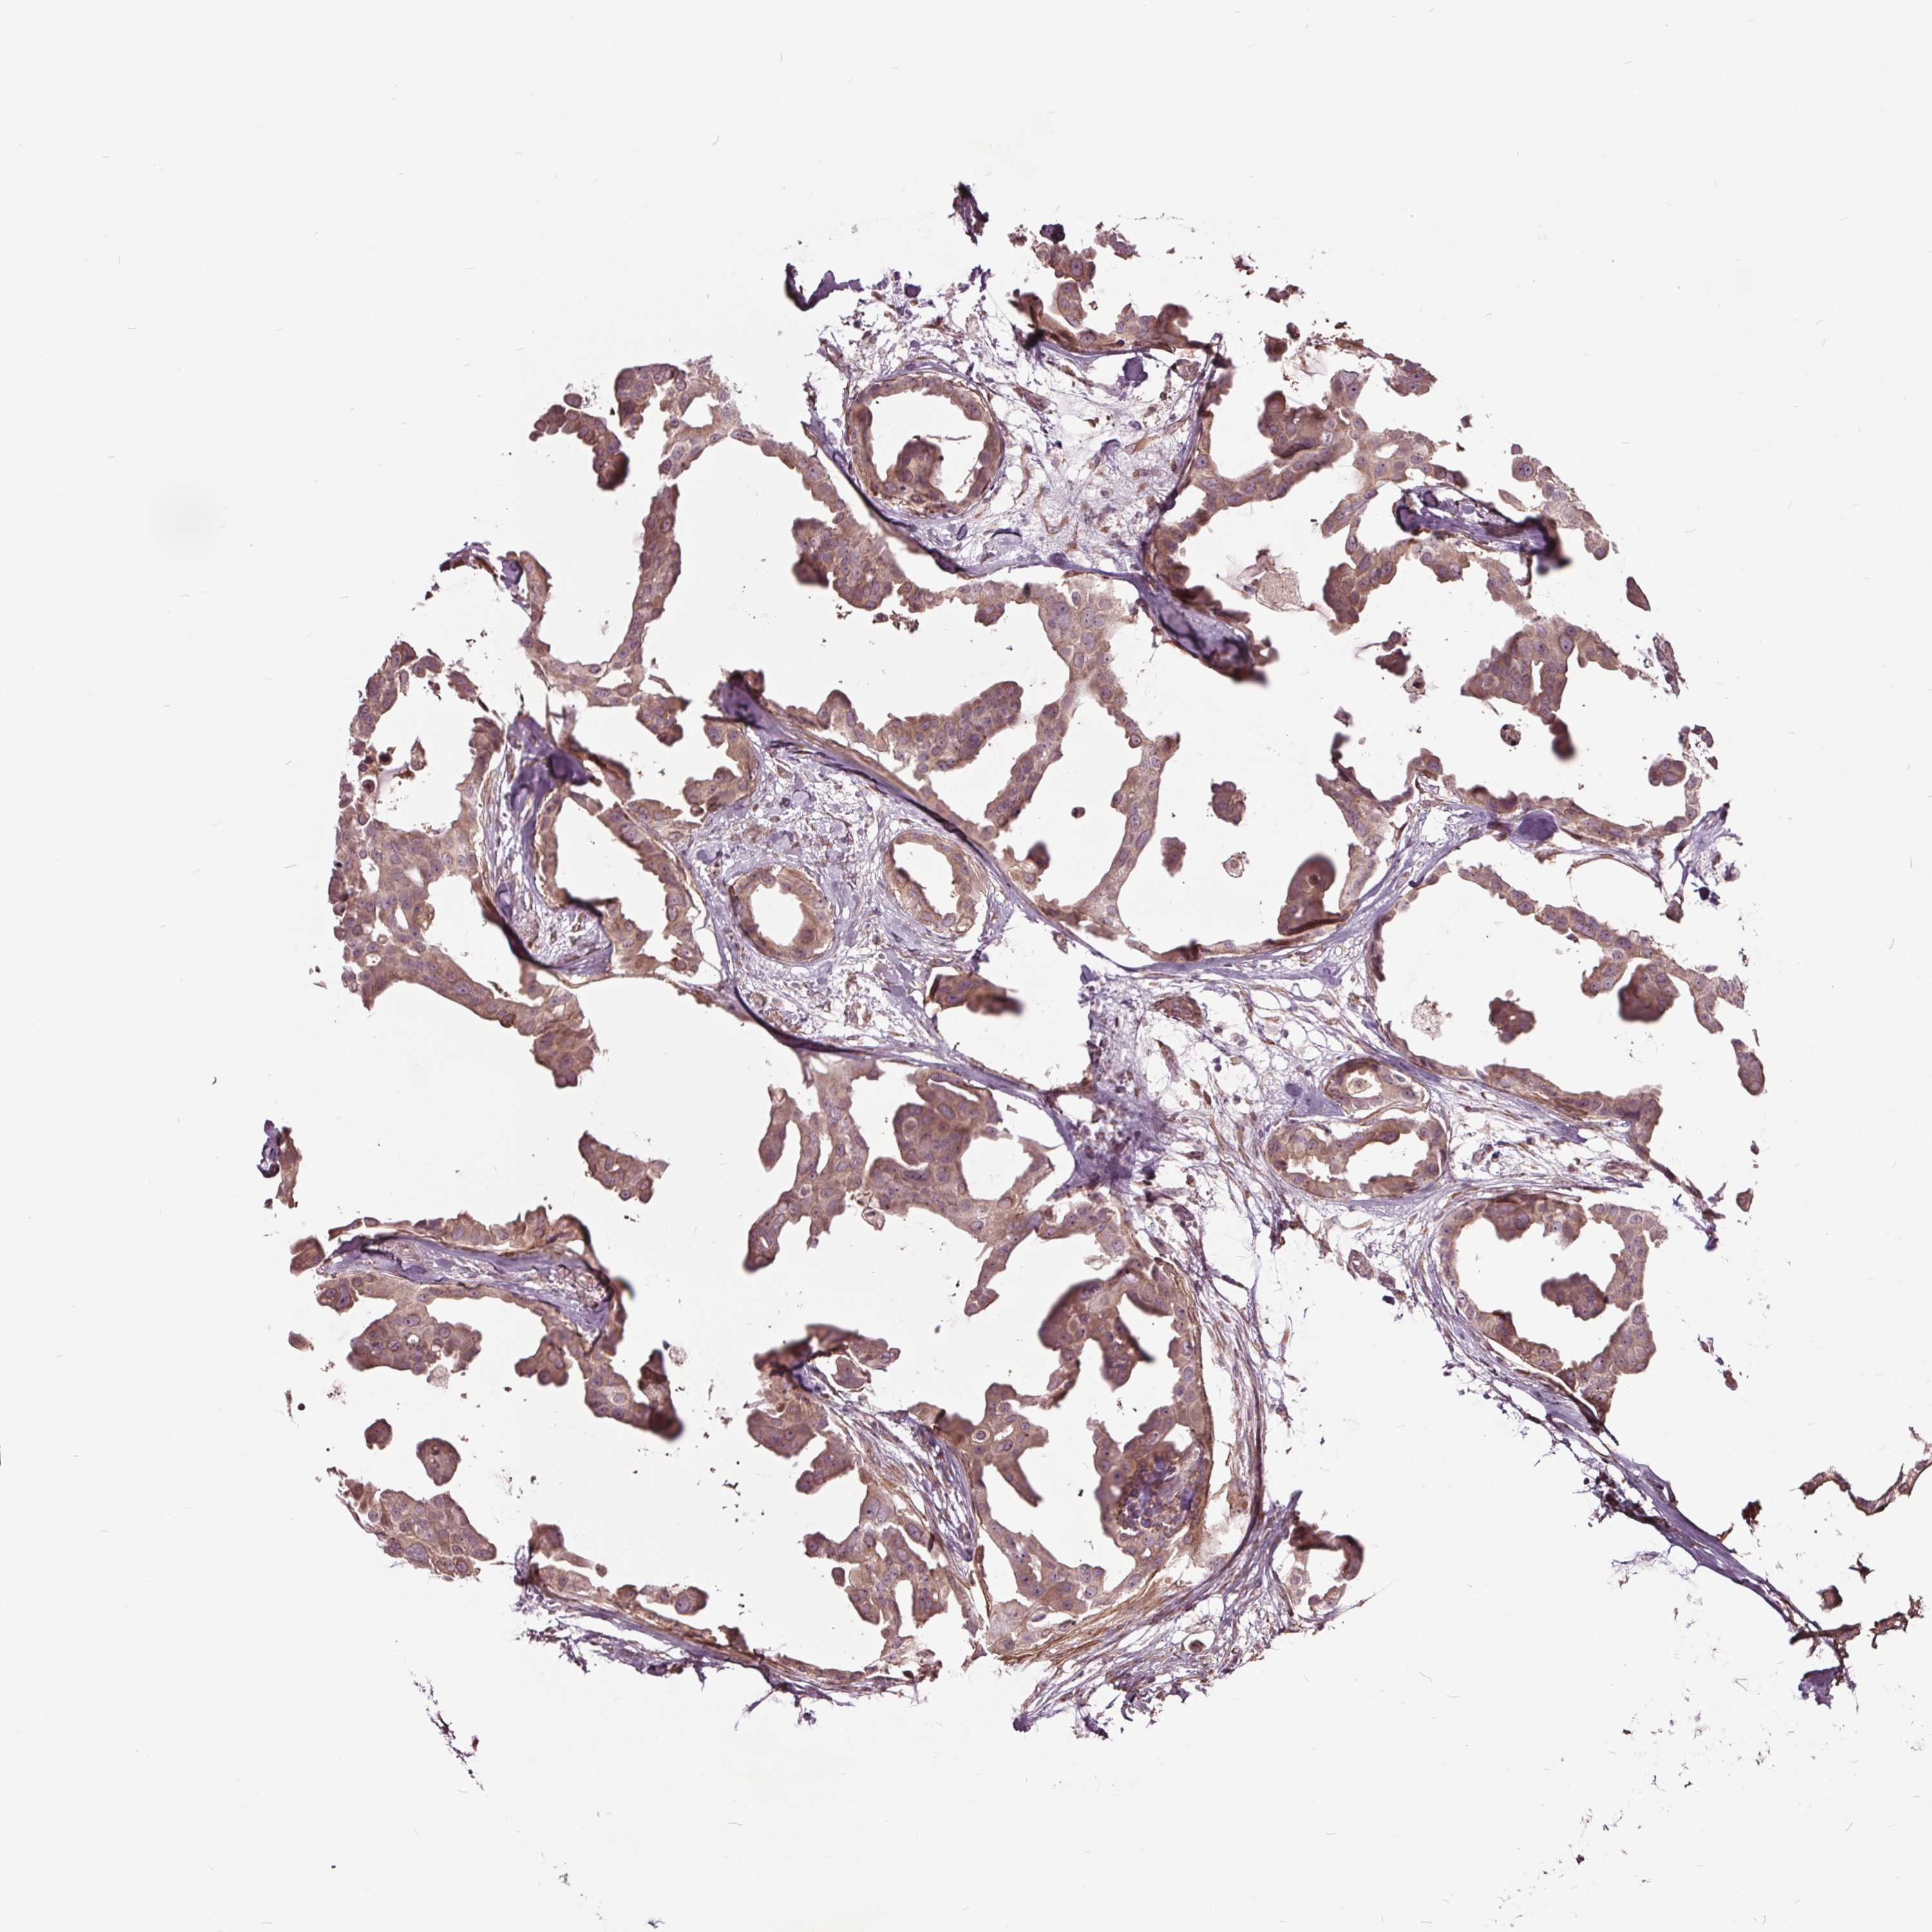

CANCER BREAST CANCER Show tissue menu

BRCA TCGA BRCA VALIDATION PROTEIN EXPRESSION

ANTIBODIES

AND

VALIDATION